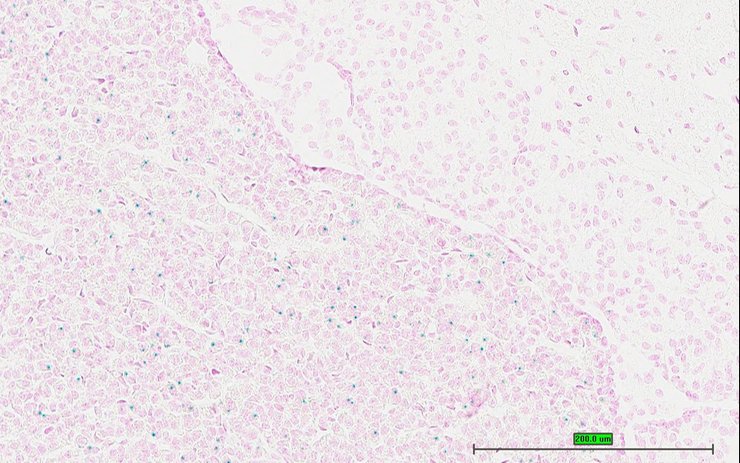

TS28: testis Present UC Davis_1881468

Specimen UC Davis_1881469: postnatal adult; Lcn10tm1.1(KOMP)Vlcg/Lcn10+ (more )

Structure Level Pattern Image Note

TS28: testis Present UC Davis_1881469